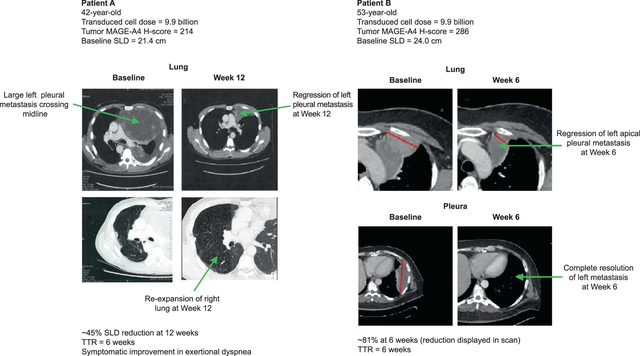

SPEARHEAD-1的I期临床试验中,有2例滑膜肉瘤患者在TCR-T细胞疗法Afami-cel治疗6周后均实现部分缓解(PR),肿瘤病变分别缩小了45%和81%。